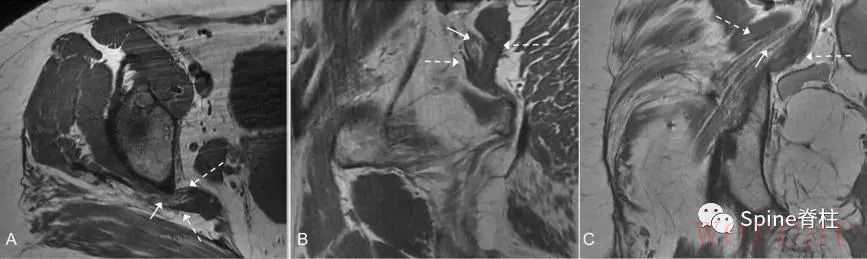

图示:MRI T1像的Beaton-Anson 3型。坐骨神经的腓总神经部分(白色细箭头)在梨状肌的后面(白色虚线箭头),胫神经部分(白色粗箭头)在前面。轴位(A)、矢状位(B)和冠状位(C)平面。

图示:MRI T1像的Beaton-Anson 4型。坐骨神经(细箭头)穿过梨状肌(虚线箭头)走行。轴位(A)、矢状位(B)和冠状位(C)平面。